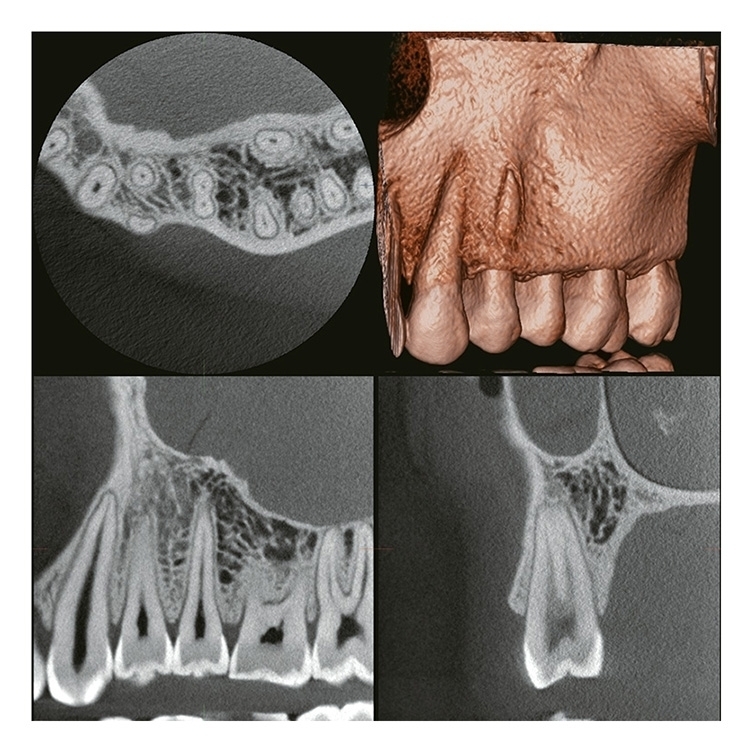

2 VERAVIEW (X800) CP (S) / (M) / (L)

Information / DemoPanorama/Cephalostat 3D & 2D

FOV bis zu: Ø 150 X H 140